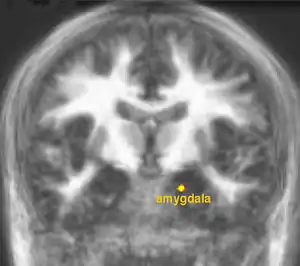

The lateral hypothalamus sends control signals to the VTA that are involved in regulation of eating behavior. The VTA and hypothalamus send regulatory signals to other brain regions such as the nucleus accumbens, orbitofrontal cortex (OFC) and the amygdala (Figure 8) that are important for control of human eating behavior, particularly in the context of learned patterns of food consumption that develop over a lifetime (see Piech et al.). For humans, Farooq et al. showed that leptin can modulate how the nucleus accumbens responds in test subjects who experience a desire to consume food, with the observed human brain activity changes corresponding to leptin-induced reduction in appetite.

Summary. Hunger plays a fundamentally important role in regulating human eating behavior. The brain can sense circulating levels of nutrients such as glucose and respond to satiety-producing hormones such as leptin. Other hormones such as grelin promote appetite. The aversive sensations associated with hunger can be produced by physiological processes such as the empty stomach being stimulated to contract. Sensory nerves carry appetite-enhancing signals to the hypothalamus and hormones such as leptin and ghrelin bind to receptors on neurons in the hypothalamus and regulate their activity. The hypothalamus acts as regulatory center for receiving orexigenic and anorexigenic signals. The hypothalamus is linked by axonal connections to other parts of the brain (such as the nucleus accumbens) that allow for reflexive control of eating in newborns. The hypothalamus is linked to other brain regions such as the amygdala and the ventral tegmental area that allow people to learn how to avoid hunger. People are usually able to learn patterns and habits of eating that are appropriate for our environment and that allow us to maintain a healthful body weight. Most research into hunger and satiety is related to health-endangering patterns of eating behavior such as under-eating and over-eating that leads to obesity.